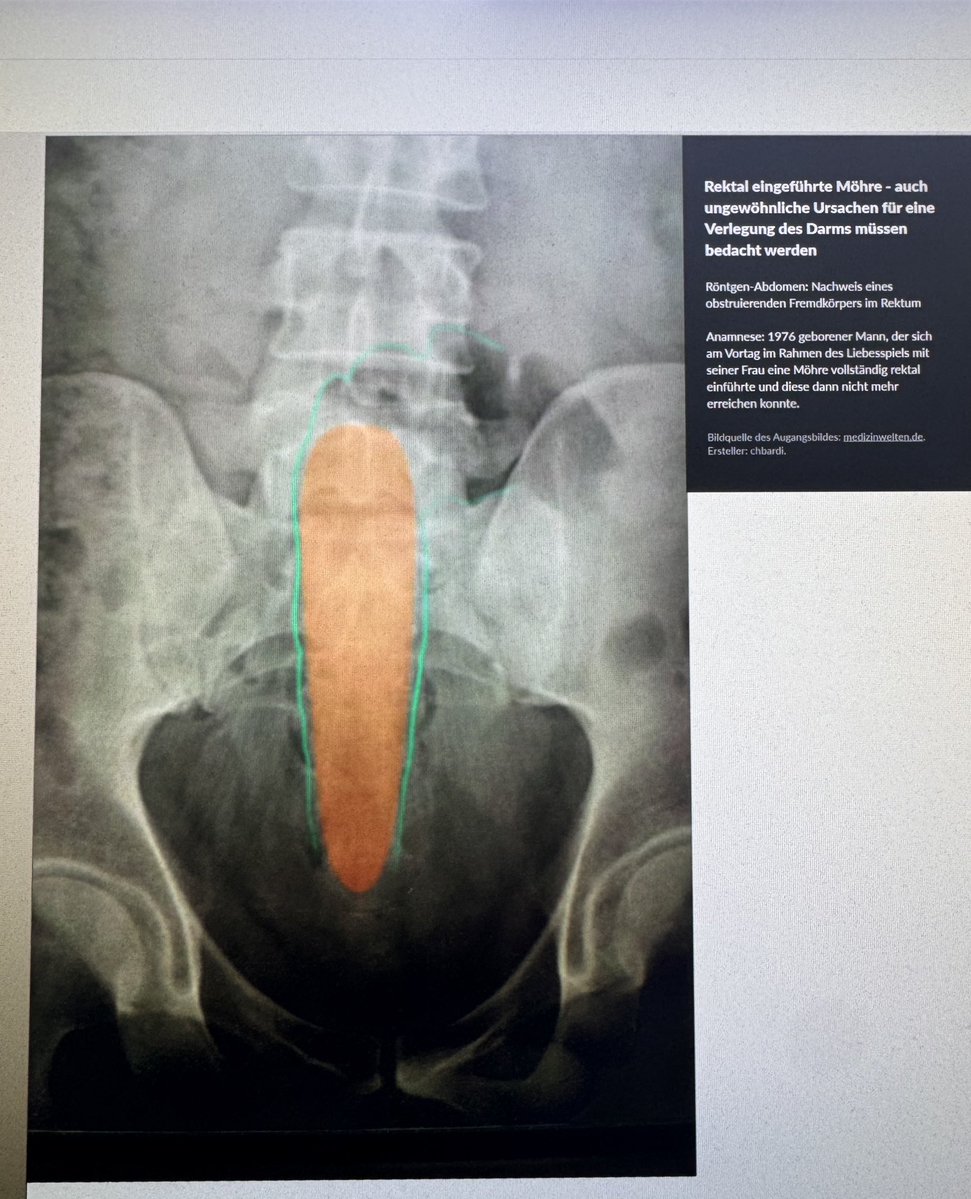

sehr nett von fler dass er seinen Fall für Studenten zur Verfügung stellt

MatFreund's tweet image. sehr nett von fler dass er seinen Fall für Studenten zur Verfügung stellt